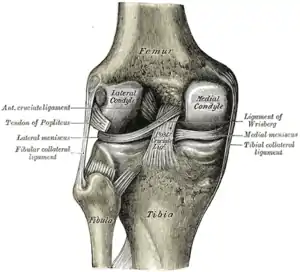

| Diagram of the right knee | |

The knee joint is formed by three bones: the femur (thighbone), the tibia (shinbone), and the patella (kneecap). These bones are held together by ligaments, which are strong bands of tissue that keep the joint stable while an individual is walking, running, jumping, etc. There are two types of ligaments in the knee: the collateral ligaments and the cruciate ligaments.

The collateral ligaments include the medial collateral ligament (along the inside of the knee) and the lateral or fibular collateral ligament (along the outside of the knee). These two ligaments function to limit sideways movement of the knee.[6]

The cruciate ligaments form an "X" inside the knee joint with the anterior cruciate ligament running from the front of the tibia to the back of the femur, and the posterior cruciate ligament running from the back of the tibia to the front of the femur. The anterior cruciate ligament prevents the tibia from sliding out in front of the femur and provides rotational stability.[6]

There are also two C-shaped structures made of cartilage called the medial meniscus and lateral meniscus that sit on top of the tibia in the knee joint and serve as cushion for the bones.[1]

|

|

| Right knee, front, showing interior ligaments | Left knee, behind, showing interior ligaments |